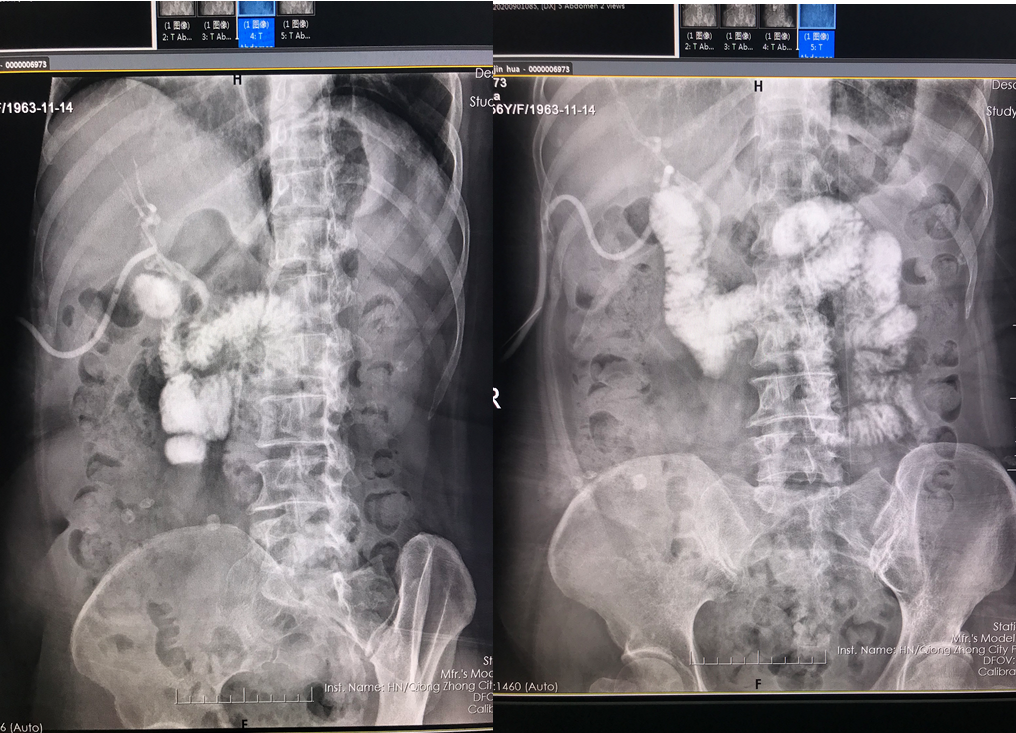

四、开展项目:科室现常规开展全身各部位CT平扫及增强检查、CT三维重建、CT血管造影(CTA、CTV)、(包括冠状动脉CTA)、CT尿路造影(CTU)、全身各部位DR摄片检查、床边摄片、同时开展胆系T管造影、CT定位下穿刺活检。

胆系T管造影